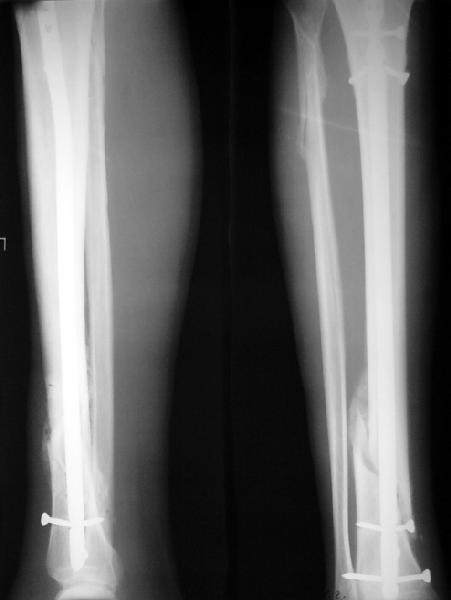

Как мне показать пример? Фото стоящего на одной оперированной конечности пациента? O! Пример, подвигнувший нас на некоторое изменение технологий. Пациент этот ходил с полной нагрузкой вопреки рекомендациям. В качестве подтверждения - сломанный проксимальный статический винт к 1 мес., а к 2 мес. - все остальные. Сейчас мы перешли на более fool-proof остесинтез.

На мой взгляд, на снимках, приведённых Вами - неправильно сростающийся перелом дистальной трети большеберцовой кости, состояние после остеосинтеза интрамедуллярным гвоздём.

Как Вы пишите снимок под номером 1 - менсяц после операции, под номером 2- два месяца после операции.

Вы не послали послеоперационный снимок, поэтому трудно судить о состоянии редукции после операции.

Установка с медиальной стороны гвоздя в области дистального фрагмента дополнительного шурупа помогло бы Вам репонировать и удержать перелом в анатомическом положении, предотвратило варусную деформацию и смещение по ширине.

Пример, приведённый Вами в нашей дискуссии по времени нагрузки после остеосинтеза не совсем удачный... Ваш больной имеет счастье, что первым согнулся проксимальный замыкающий винт, а не дистальный и гвоздь не пенетрировал голеностопный сустав.

I think that the X-Rays show S/P IMN of Spiral # of the Distal Tibia consoles in misalignment.

You wrote that a picture number 1 - f month after the surgery, and number 2-two months after the surgery.

You have not sent a postoperative X-Rays; so it's impossible to discuss about the condition of a reduction after operation.

Let to express concerning technique of operation my opinion... Insertion of a screw to medial side of a nail in distal fragment would help you to reduction and to keep this fracture in anatomic position has prevented varus deformity and displacement on width. By the way, if it is possible send a postoperative picture.

Your patient is lucky enough, that by the first was bent proximal locking screw, instead of distal and a nail does not penetrate to the ankle joint.